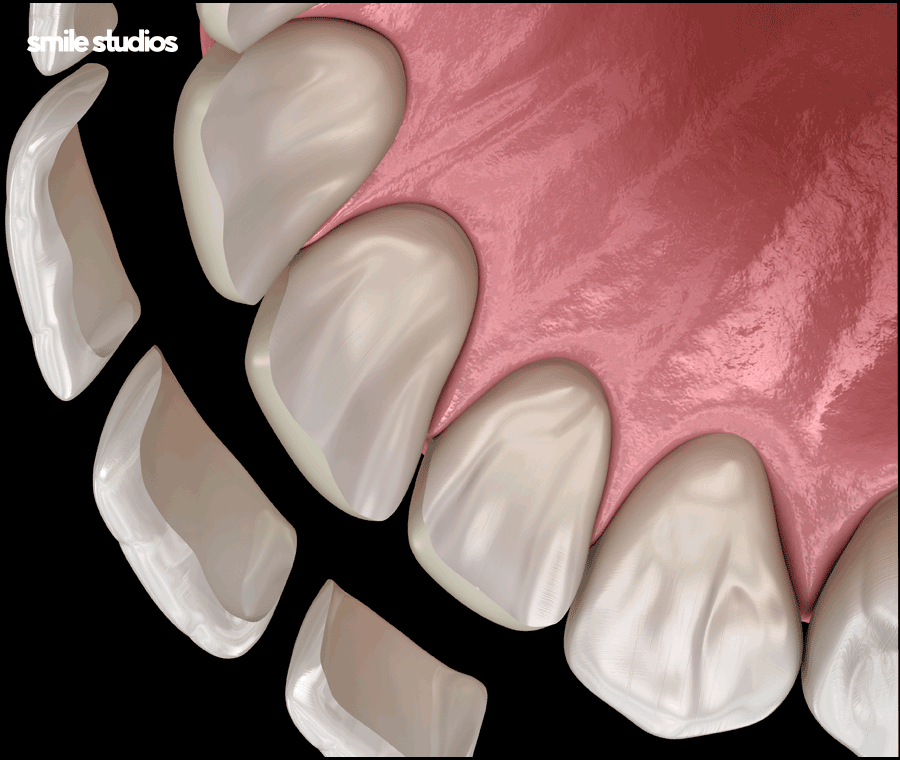

그중 라미네이트는 심미성과 기능을 동시에 만족시키는 해결책 중 하나로 주목받고 있는데요.

손상된 치아 앞면을 얇게 다듬거나 혹은 삭제하지 않고 세라믹 재질의 보철물을 제작해 부착하는 방식입니다.

심미적으로 문제가 되는 부분을 감추면서 모양, 색상을 개선할 수 있는 비침습적 심미치료입니다.

과거처럼 많은 부분을 삭제하지 않고도 미세하게 다듬거나 깎아내지 않고도 진행이 가능한데요.

이를 통해 영구치를 보존하면서도 적용이 가능해 삭제에 대한 부담을 줄일 수 있습니다.